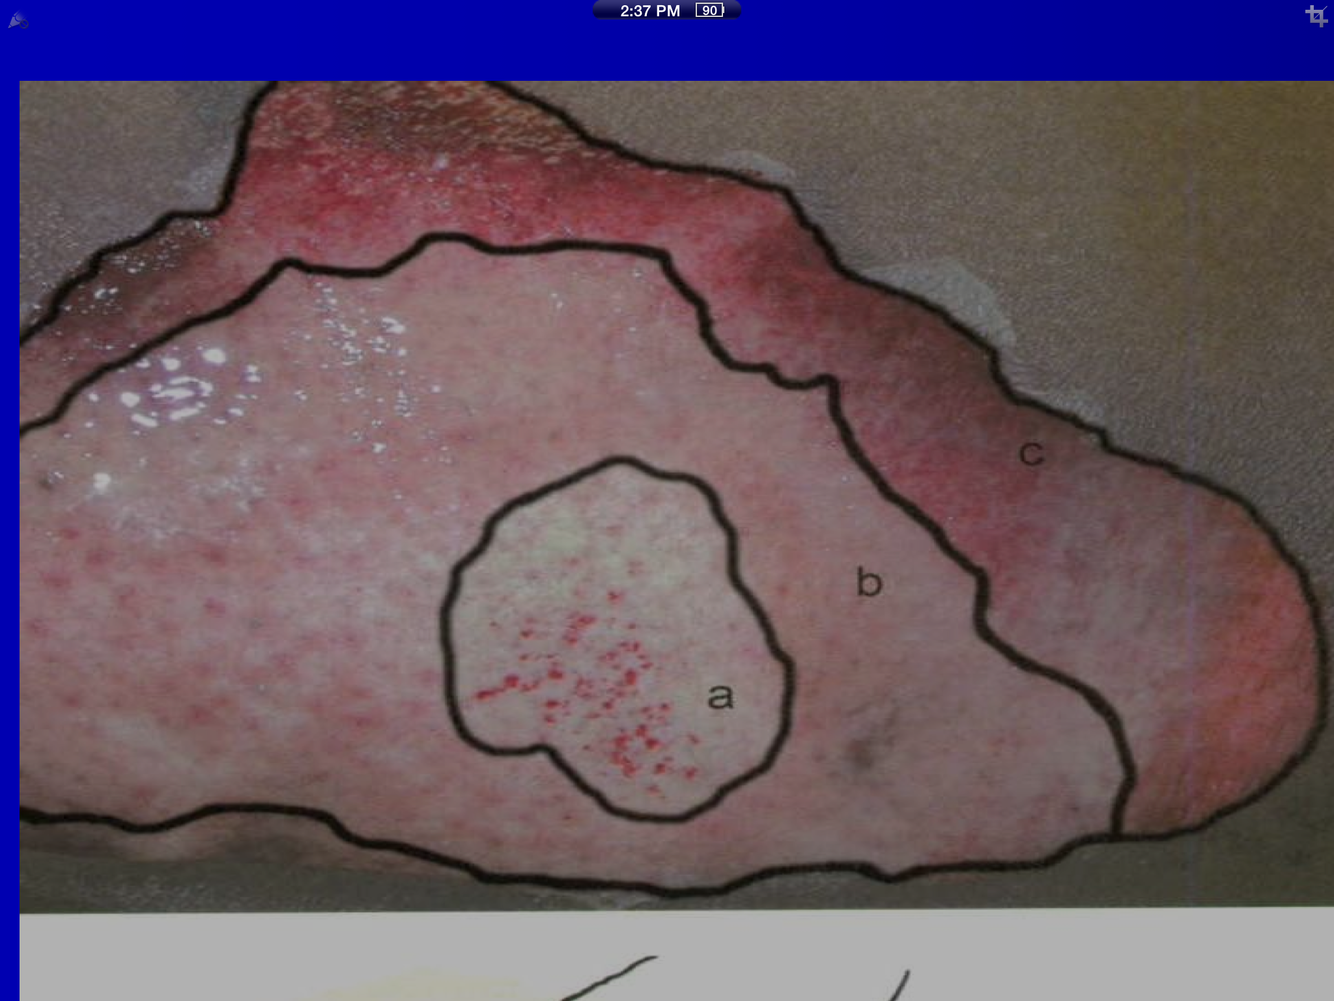

Name and describe the 3 zones of cellular damage in burns.

a. coagulation: usually where the heat source was strongest, tissue is dead and has undergone coagulation necrosis

b. Stasis: tissue that is damaged but not dead, proper treatment can allow full recovery

c. Hyperemia: vasodilation of medium and small arteries in the dermis turns the tissue red and inflammation can damage this tissue, however, proper care allows full recovery